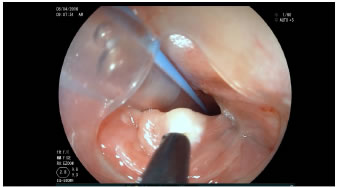

Previa firma de consentimiento informado, se practicó el procedimiento en salas de cirugía y bajo anestesia general. Con el paciente en decúbito lateral izquierdo, inicialmente se hace la esofagogastroduodenoscopia, identificándose el divertículo y llegando al antro gástrico, donde se avanza una guía hidrofílica. A través de esta, se avanza una sonda orogástrica la cual se fija a la comisura oral (figura 2).

Figura 2. A la izquierda, se observa la luz esofágica con la guía

hidrofílica y, a la derecha, la luz del divertículo.

Usando CO2, una vez identificado el tabique que separa el divertículo de la luz del esófago, se secciona el tabique con el papilótomo de punta, incluyendo las fibras musculares hasta el límite endoscópico visible (figuras 3 y 4). Durante la sección se usa el capuchón, el cual facilita la visualización del tabique y separa las paredes tanto del divertículo como del esófago. Se controla el sangrado, en caso de presentarse, con las técnicas endoscópicas usuales (electrocoagulación, inyección o clips). Se retira la sonda orogástrica. No se usan antibióticos profilácticos.